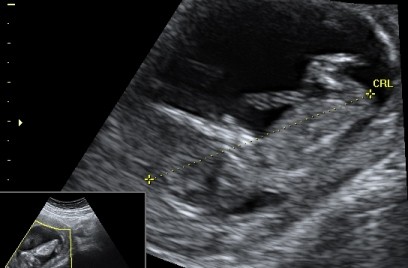

Maleństwo 12 t 4 dc. Tylko wiercipięta z Niego straszna

, dlatego takie rozmazane zdjęcie: